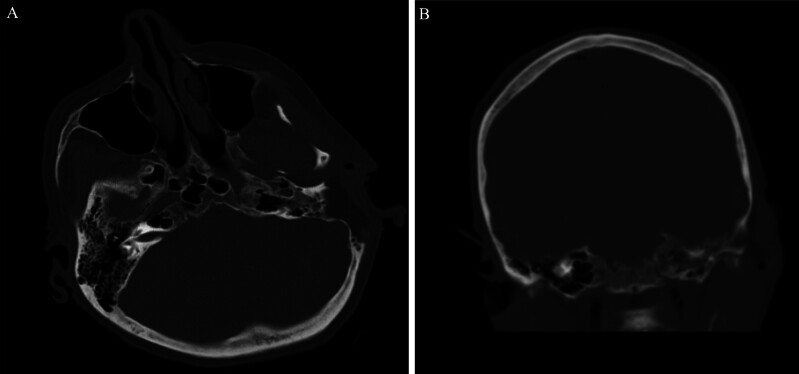

Background: Spontaneous pneumocephalus is a rare, but potentially serious condition often secondary to a CSF leak. This egress of CSF causes an inward movement of air to replace the lost volume. CSF leaks are typically posttraumatic and present as rhinorrhea or otorrhea. Locating the bony defect and herniating contents through imaging is crucial for planned surgical intervention. In this report, the author present the case of a patient with progressive spontaneous pneumocephalus with an apparent but unidentifiable CSF leak.

Observations: A 76-year-old female presented to the authors' institution with rapidly progressing spontaneous pneumocephalus. This case is unique in that the patient's pneumocephalus continued to expand without any radiological indication of extracranial CSF, leading us to believe that the CSF was intermittently leaking through the eustachian tube and passing down the patient's oropharynx. Given the presumed pathway, an initial conservative surgical approach was chosen for this patient's spontaneous pneumocephalus instead of the traditional middle cranial fossa or transmastoid approach.